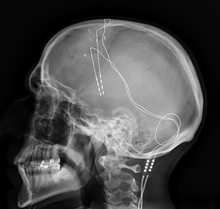

- How Action Potential is Measured in a Neuron

In order to determine the voltage of the neuron, two microelectrodes are typically inserted into the neuron, with one connected to a stimulator while the other one is connected to a voltmeter to measure the voltage2. The electrode stimulator is often connected to a battery, which corroborates the idea that an external energetic force needs to be applied to the battery in order for an action potential to occur. This electrode stimulator can either add a positive voltage or negative voltage to the neuron, showing the depolarizations and polarizations of the neuron.

Closed-Loop Neuromodulation, also known as an intelligent neuromodulation, is a flexible neural device that sends a signal in response to a biomarker. This focused delivery of a stimulus to neural tissue whose intent is to affect neural or physiological processes helps researchers understand more about human physiology1. A certain biomarker threshold has to be met in order for the closed-loop neuromodulation to be activated, meaning that this device acts as a Responsive Neurostimulation (RNS)2. RNS differs from Deep Brain Stimulation (DBS) since DBS is created to reduce the frequency of brain malfunction while RNS targets specific malfunctions at the time of their occurrence. If you want to learn more about DBS, take a look at my other blog, Deep Brain Stimulation – A Neurorehabilitation Method for Parkinson’s Patients. Closed-loop neuromodulation encapsulates RNS, DBS, and Vagus Nerve Stimulation (VNS). An early example of closed-loop neuromodulation is its application in refractory epilepsy. Refractory epilepsy is when the seizures are unable to be controlled by medication or when the condition is too severe, warranting the therapeutic use of closed-loop neuromodulation. Once implanted, when a seizure begins in the patient, the electrodes stimulate certain areas of the brain to stop the episode3. In the beginning, an open-loop neuromodulation was used, a system whose response is dependent on a timed algorithm rather than in response to a neural stimulus. These systems are set by a neurologist and require multiple appointments. As can be presumed, the closed-loop neuromodulation is much more effective in its response since it is able to immediately respond to the biomarker stimulus instead of only being activated at scheduled times2.

Responsive Neurostimulation (RNS) is a method that monitors electrical irregularities in the brain. It is an invasive method where a neurostimulator is implanted into the brain and is connected to wires that extend into areas of the brain where seizures occur. When triggered, it delivers a brief pulse of electrical stimulation through the leads. RNS is a great rehabilitative method, because it can be used to supplement epilepsy treatment and can be removed at any point5. How this device works as a treatment for epilepsy is that it disrupts the “electrical storm” that occurs in the brain when a seizure occurs. This intervention alleviates the amount of electrical stimulation and may even circumvent a seizure altogether6. Vagus Nerve Stimulation (VNS) intends to alter the activity of nerves by having an implanted device that sends mild pulses of electrical energy to the brainstem through the vagus nerve. Once it reaches the brainstem, the electrical charge disseminates across the brain and changes how brain cells work. VNS is believed to improve blood flow in critical areas of the brain, alter the electrical stimulations that occur when a person is having a seizure, and increase the level of neurotransmitters that control seizure development7.

Deep Brain Stimulation, originating in the late 1980’s, is a revolutionary discovery that currently works as a treatment for movement disorders. Deep Brain Stimulation is an invasive procedure in which electrodes are implanted into certain areas of the brain, allowing for an electrical current to stimulate the brain. The intention of Deep Brain Stimulation is to interrupt the abnormal signaling that occurs in Parkinson’s patients, such as tremors, by sending an electrical impulse. The electrodes are specifically implanted in target areas of the basal ganglia – a subcortical nuclei primarily responsible for motor control – such as the subthalamic nucleus or globus pallidus internus. The subthalamic nucleus is in charge of motor regulation, while the globus pallidus internus is responsible for inhibiting the ventral lateral nucleus and ventral lateral nucleus of the thalamus. To elaborate, the function of this portion of the brain is regulation of motor movement, since the areas it inhibits are centers for motor control7. This is done to change the activity between the direct and indirect basal ganglia pathways to promote motor movement without the dopamine6.